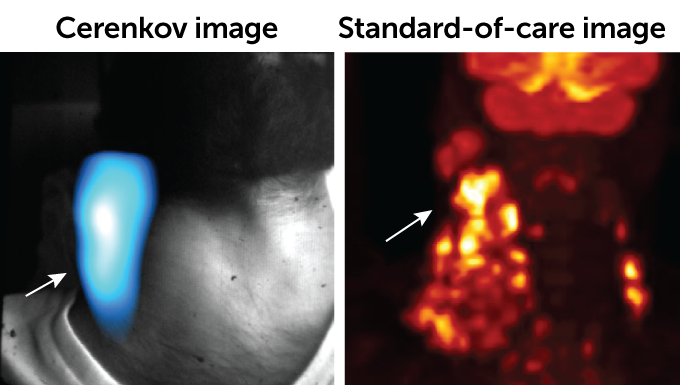

Cerenkov light, generated by high-speed particles traveling faster than light through a material, emits a blue glow. The light can be used to image a variety of cancers, new research shows.

When compared with standard scans of the tumors, the Cerenkov light images were classified as “acceptable” or higher for 90 percent of patients, says Magdalena Skubal, a cancer researcher at Memorial Sloan Kettering Cancer Center in New York City.

CLI images aren’t as precise as those from PET/CT scans. But CLI could be used as an initial diagnostic test or to assess the general size of a tumor undergoing treatment, says study coauthor Edwin Pratt, also of Memorial Sloan Kettering Cancer Center. “It would be a quick and easy way to see if there’s something off … [that warrants] further investigation,” Pratt says.